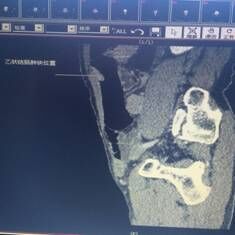

我院胃腸外科今年3月收治一名男性患者,以反復腹痛7月入院,CT提示胃竇部及乙狀結腸占位性病變(分別見圖1、2),行內(nèi)窺鏡活檢分別考慮胃腺癌以及乙狀結腸絨毛狀腺瘤,不排除惡變傾向。為改善患者生存率,減少創(chuàng)傷,手術團隊決定充分發(fā)揮腹腔鏡技術優(yōu)勢,采用腹腔鏡下一期同時切除胃、結腸病變,由于患者乙狀結腸病變惡性診斷不明確,根據(jù)腫瘤根治的原則,先處理乙狀結腸。手術當中依據(jù)冰凍切片,在腹腔鏡下首先完成乙狀結腸癌根治,后行腹腔鏡下遠端胃癌根治術。一次微創(chuàng)手術,切除兩個腫瘤,免除了患者傳統(tǒng)剖腹手術及二次手術的創(chuàng)傷,縮短了住院時間,術后恢復快,降低了患者住院費用。

圖片1                               圖片2